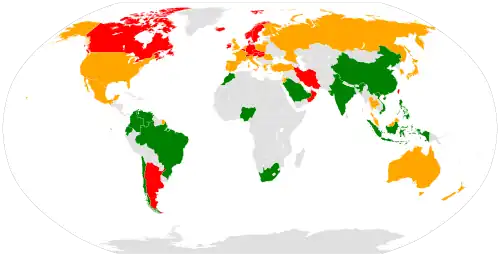

Epidemiology

Hip fractures are seen globally and are a serious concern at the individual and population level. By 2050, it is estimated that there will be six million cases of hip fractures worldwide.[59] One study published in 2001 found that in the US alone, 310,000 individuals were hospitalized due to hip fractures, which can account for 30% of Americans who were hospitalized that year.[60] Another study found that in 2011, femur neck fractures were among the most expensive conditions seen in US hospitals, with an aggregated cost of nearly $4.9 billion for 316,000 inpatient hospitalizations.[61] Rates of hip fractures are declining in the United States, possibly due to increased use of bisphosphonates and risk management.[62] Falling, poor vision, weight, and height are all seen as risk factors. Falling is one of the most common risk factors for hip fractures. Approximately 90% of hip fractures are attributed to falls from standing height.[63]

Population

All populations experience hip fractures but numbers vary with race, gender, and age. Women have three times as many hip fractures as men.[65] In a lifetime, men have an estimated 6% risk whereas postmenopausal women have an estimated 14% risk of having a hip fracture.[66] These statistics provide insight over a lifespan, and conclude that women are twice as likely to have a hip fracture. The overwhelming majority of hip fractures occur in white individuals, while blacks and Hispanics have a lower rate of them. This may be due to their generally greater bone density and also because whites have longer overall lifespan and higher likelihood of reaching an advanced age where the risk of breaking a hip goes up.[66] Deprivation is also a key factor: in England, it has been found that people in the poorest parts of the country are more likely to fracture a hip and less likely to recover well than those in the least deprived areas.[67]

Age related

Age is the most dominant factor in hip fracture injuries, with most cases occurring in people over 75. The increase of age is related to the increase of the incidence of hip fracture,[59] which is the most frequent cause of hospitalization in centenarians, overcoming congestive heart failure and respiratory infection.[68] Falls are the most common cause of hip fractures; around 30–60% of older adults fall each year. This increases the risk for hip fracture and leads to the increased risk of death in older individuals, the rate of one year mortality is seen from 12 to 37%.[69] For those remaining patients, half of them need assistance and cannot live independently. Also, older adults sustain hip fractures because of osteoporosis, which is a degenerative disease due to age and decrease in bone mass. The average age for sustaining a hip fracture is 77 years old for women and 72 years old for men.[70]